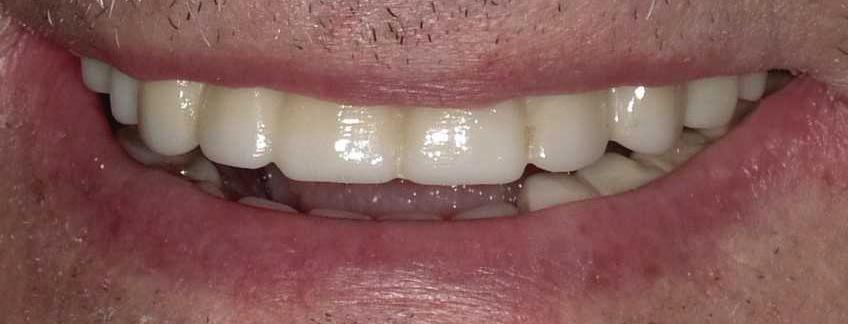

Submitted By Sivakumar Sreenivasan, DMD, MDS

Dental Implant Center of Rockville

Can just four implants replace all of the teeth on the top or the bottom of your mouth? Thanks to advances in dental implant technology, that answer is a resounding yes.

Believe it or not, tooth loss is extremely common among adults, especially as we age. In fact, more than 35 million people in America are missing all of their upper and/or lower teeth. Rather than living with the discomfort and hassles of dentures, many people are opting for what is called “all-onfour” dental implant restoration.

All-On-Four: One Full Arch Of Teeth, Four Dental Implants

Here’s where it gets really interesting: You do not need a dental implant for each and every one of your missing teeth. All you need is four precisely placed implants on the top of your mouth, and four on the bottom, to restore your full smile. That’s the beauty of the all-on-four. And because the implant is made of titanium, it has the unique ability to fuse to living bone and function as part of it. So eventually, the dental implant becomes part of the jawbone and serves as a strong, long-lasting foundation for your new teeth.

this bone fusion has another important benefit: it prevents future bone loss in the jaw. This helps to maintain a more youthful facial structure – and better oral health. But perhaps the biggest surprise about the all-on-four is how quickly it can transform your life.